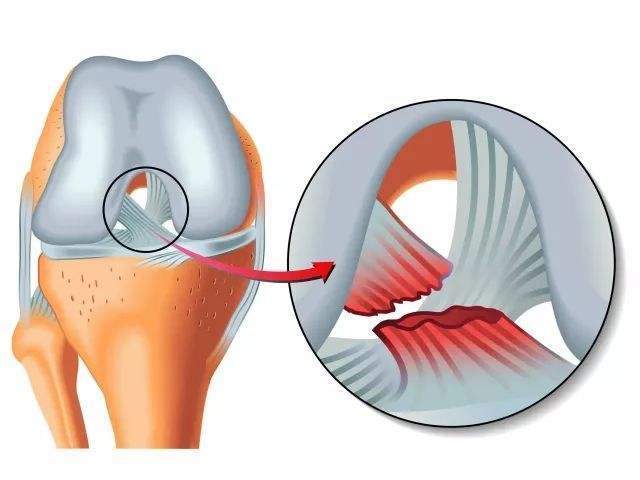

前十字韧带

膝关节十字韧带又称交叉韧带,位于股骨内外髁之间,前后两条,互相交叉。前十字韧带,位于膝关节内,连接股骨与胫骨(起于股骨髁间窝外后部,向前、内、下止于胫骨棘前侧),主要作用是限制胫骨向前过度移位。后十字韧带

前十字韧带损伤

膝关节过伸或过度外翻可引起膝关节前十字韧带损伤。如为过度外翻引起,可同时发生内侧付韧带断裂。前十字韧带损伤合并内侧半月板损伤也较常见。后十字韧带损伤